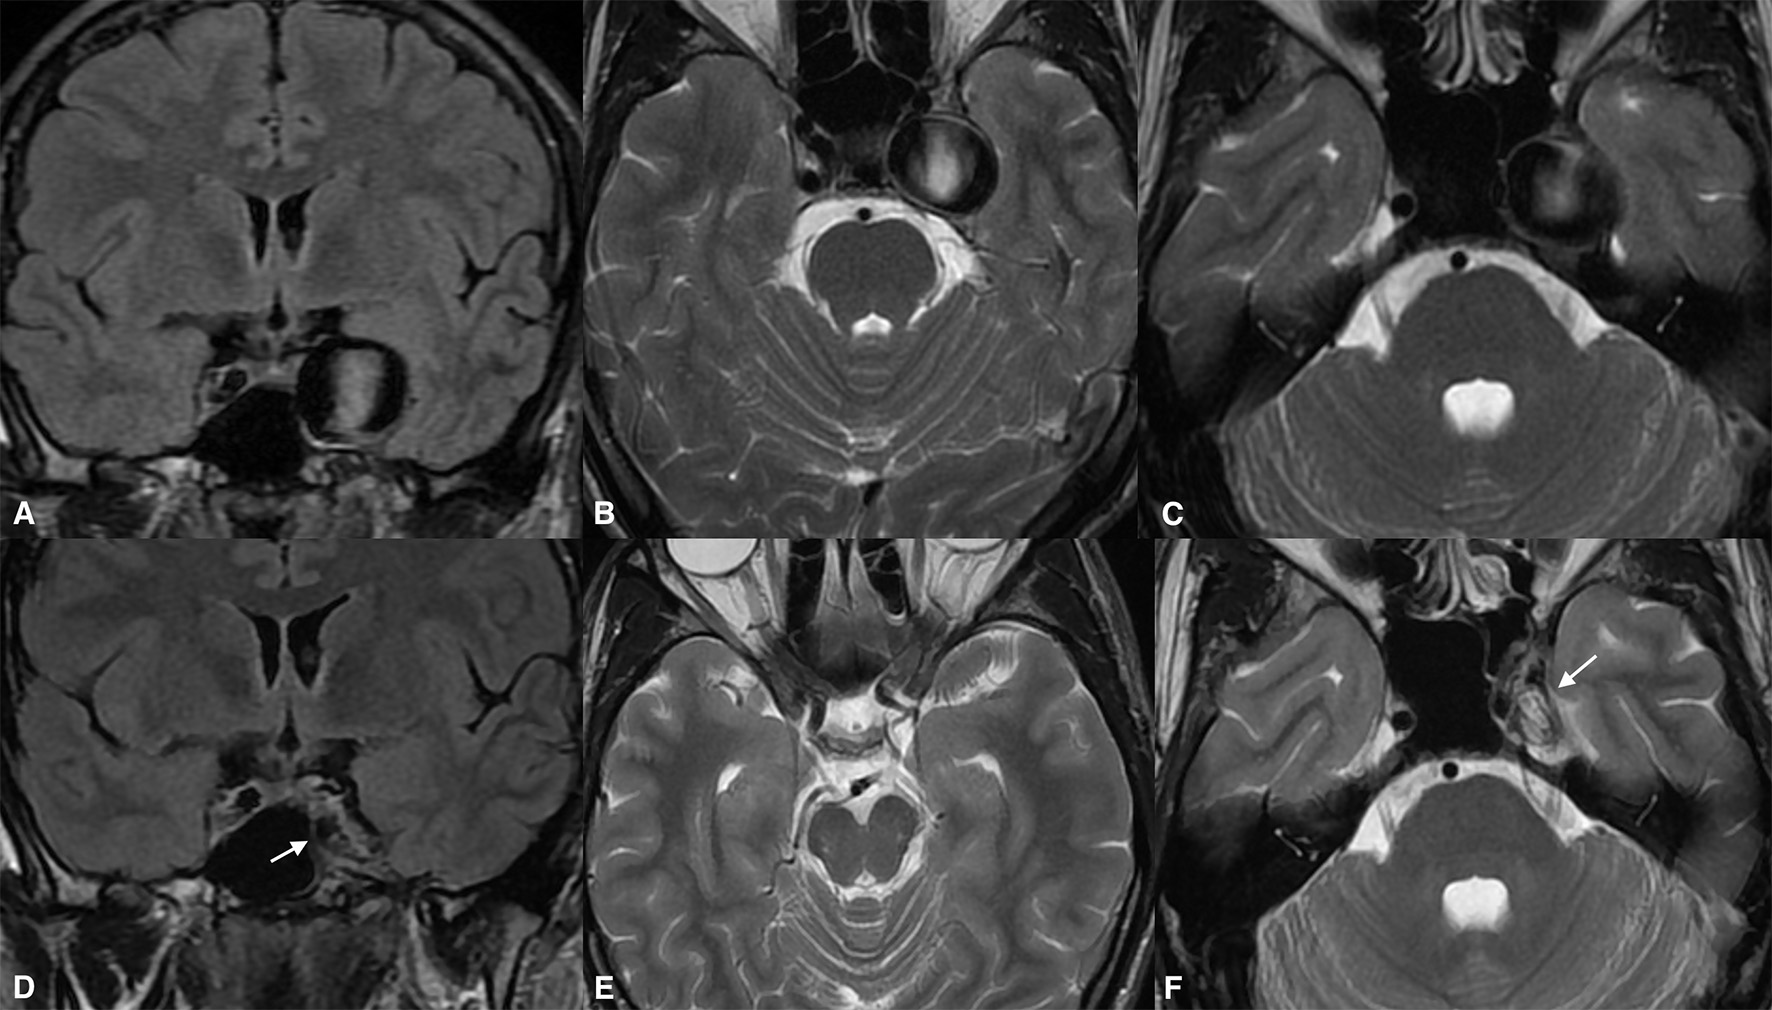

Data for the 24 month follow-up were available for 33 patients. At that point, 31 of the aneurysms had become entirely obliterated, and entry filling of the aneurysms (OKM grade C) was observed in only two cases. The MRI examinations revealed that 32 of the aneurysms demonstrated aneurysmal shrinkage, by a mean of 3,917 mm3 with respect to baseline (mean 47% volume loss). A comparison of results between the second and third follow-ups demonstrated that only 16 aneurysms continued to diminish (Figures 3, 4). No aneurysmal regrowth or adverse changes were found in their morphology at that point.

Figure 3

Giant cavernous internal carotid artery aneurysm causing diplopia from oculomotor nerve involvement (A). The same aneurysm was causing a slight mass effect over the left temporal lobe and the adjacent brain tissue (B,C). Twenty-four months after the treatment, the magnetic resonance imaging [(D), arrow] demonstrated aneurysmal collapse (E) and elimination of the mass effect. Note the absolute shrinkage of the aneurysm with a volume reduction of up to 70% of its previous volume, as seen on the long-term follow-up [(F), arrow].

Most of the patients demonstrated clinically significant improvements in their presenting symptoms after treatment. At the last follow-up, all 13 patients who had presented with third cranial nerve palsy showed improvements. Symptoms had resolved entirely in nine patients; one patient had minor diplopia due to persistent misalignment of the affected eye; and two had mild but ameliorated ptosis. Complete reversal of the pretreatment edematous changes was confirmed in all cases showing substantial mitigation of headaches. Quadriparesis in one patient presenting with brain stem compression and obstructive hydrocephalus was entirely resolved by the first clinical follow-up. Figure 5 provides the radiological data of the aforementioned case. Unfortunately, only two patients completely recovered from visual deficits due to optic or chiasmal compression. Among the remaining patients with presenting visual symptoms in two, vision improved from as low as finger counting to vision of 0.6.

Figure 5

Giant partially thrombosed cerebral aneurysm causing quadriparesis and obstructive hydrocephalus due to brain stem compression (A,D). Significant post-treatment clinical improvement was confirmed due to alleviation of the brain stem compression (B,C). The ongoing collapse of the aneurysmal sac with progressive intrasaccular T2WI signal changes was noted during the long-term follow-up (E,F).